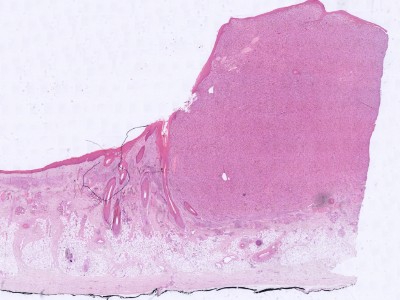

Histologie:De tumor gaat uit van de dermis en is ongekapseld.

Er zijn talloze spoelcellige atypische cellen aanwezig in een wanordelijk patroon,

met meerdere mitosefiguren. Daartussen grote multinucleaire reuscellen die vet

bevatten. Kleuringen kunnen helpen (vimentine +, cytokeratine -, S-100 -, desmin/SMA

-, LN2). Er bestaat ook een

van het atypisch fibroxanthoom.

![Histologie atypisch fibroxanthoom (click on photo to enlarge) [source: Kevin Kwee / Afdeling Pathologie MUMC] Histologie atypisch fibroxanthoom](../../../pacoupes/thumbnails/atypisch-fibroxanthoom.jpg) |

ingescande coupe (zoom) |

Bron

hoge resolutie PA-foto: Kevin Kwee en Afdeling Pathologie MUMC. Klik

op de afbeelding om in te zoomen.